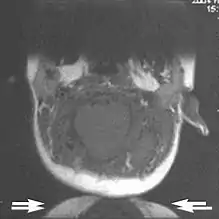

Metal artifacts occur at interfaces of tissues with different magnetic susceptibilities, which cause local magnetic fields to distort the external magnetic field. This distortion changes the precession frequency in the tissue leading to spatial mismapping of information. The degree of distortion depends on the type of metal (stainless steel having a greater distorting effect than titanium alloy), the type of interface (most striking effect at soft tissue-metal interfaces), pulse sequence and imaging parameters. Metal artifacts are caused by external ferromagnetics such as cobalt containing make-up, internal ferromagnetics such as surgical clips, spinal hardware and other orthopaedic devices, and in some cases, metallic objects swallowed by people with pica.[3] Manifestation of these artifacts is variable, including total signal loss, peripheral high signal and image distortion (Figs 3 and 4).[1] Reduction of these artifacts can be attempted by orientating the long axis of an implant or device parallel to the long axis of the external magnetic field, possible with mobile extremity imaging and an open magnet. Further methods used are choosing the appropriate frequency encoding direction, since metal artifacts are most pronounced in this direction, using smaller voxel sizes, fast imaging sequences, increased readout bandwidth and avoiding gradient-echo imaging when metal is present. A technique called MARS (metal artifact reduction sequence) applies an additional gradient, along the slice select gradient at the time the frequency encoding gradient is applied. ==Signal processing dependent artifacts== The ways in which the data are sampled, processed and mapped out on the image matrix manifest these artifacts.[1]